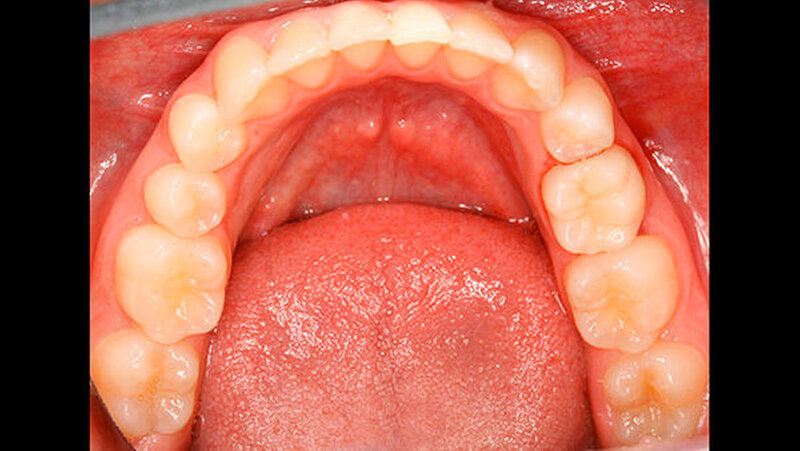

Da die junge Patientin bisher keine Restaurationen benötigt hatte, sprach sie sich vehement für eine möglichst wenig oder sogar non-invasive Vorgehensweise aus. Weil der Zahn 75 prinzipiell völlig intakt war, sich nur eben im Vergleich zu den benachbarten permanenten Zähnen in Infraokklusion befand, war das primäre Ziel der Restauration, diesen in maximale Interkuspidation zu bringen. Deshalb wurde vereinbart, die bis zur Interkuspidation fehlende Zahnhartsubstanz - etwa ein Drittel der klinisch sichtbaren Krone - durch ein Onlay auszugleichen. Diese Lösung entsprach zusätzlich dem Wunsch der Patientin, nach Möglichkeit eine non-invasive Behandlung zu erhalten.

Unmittelbar nach der Entbänderung erfolgte deshalb die Abformung beider Kiefer (Aquasil Ultra Heavy und Aquasil Ultra LV, Dentsply DeTrey) sowie eine Bissnahme im Schlussbiss (Futar Fast (1:1), Kettenbach GmbH). Im Labor erfolgte die Herstellung eines Overlays aus Komposit (SR Adoro, Ivoclar Vivadent) (Abbildungen 4 bis 6), das etwa zehn Tage nach der Abformung eingesetzt wurde.

Anschießend wurde der Zahn okklusal und auf den bukkalen und lingualen Höckerabhängen mit 35-prozentiger Phosphorsäure geätzt. Es folgte die Applikation des Bondings (Optibond FL, Kerr Hawe) sowie die Applikation eines dual-härtenden Befestigungssystems auf Kompositbasis (BiFix QM, VoCo). Zuletzt wurden die Ränder der Restauration sowie die Übergange zum Zahn geglättet (Brownie und Greenie, Shofu Dental GmbH) und die Okklusion überprüft (Abbildungen 7 und 8).